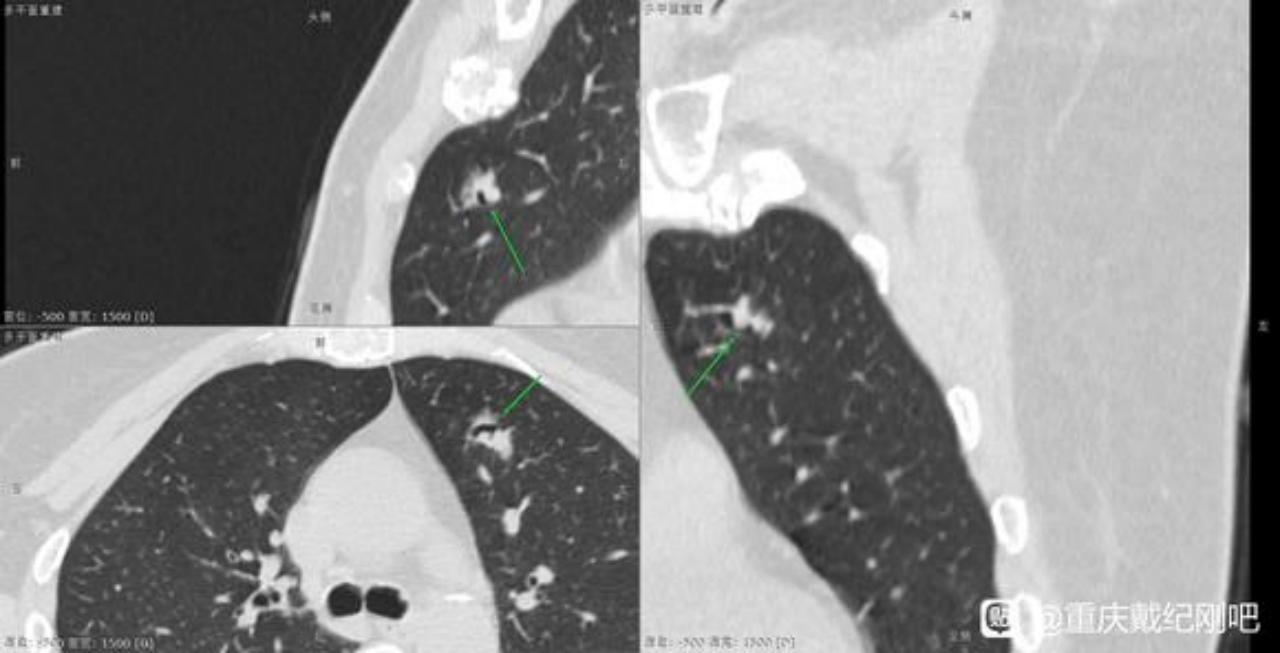

左肺上叶已切除的混杂磨玻璃密度结节影CT图像和诊断截图:

PET-CT的结果和截图: